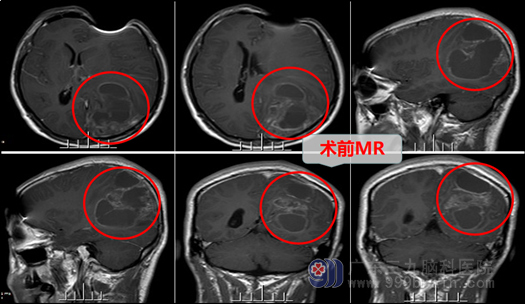

周先生今年42岁,可是这个月以来记性越来越差,总是丢三落四,出门忘记带钥匙,骑电动车忘记锁车等等,双眼还有视物不清,去当地眼科医院看了,滴了眼药水,也没有好转。女儿跟周先生开玩笑说,是不是老年症状提前,变中年痴呆了。可是后面还总是说头痛,女儿才觉得不对劲,带着周先生去当地医院看病,查了头颅CT显示:“左侧顶枕叶异常密度,多考虑恶性病灶合并出血可能”。经邻居介绍,得知了广东三九脑科医院神经外十科专业性,在颅脑肿瘤这方面具备很大的权威性。于是慕名来到了广东三九脑科医院神经外十科。

在入住神经外十科后,以欧阳辉主任为首的神经外十科医疗组积极完善术前准备,再经过详细认真的术前讨论后,经家属同意,在5-12日进行左侧颞顶枕叶占位病变切除术。左侧是优势半球,除管理右侧肢体的运动外,还负责病人的语言,如损伤这部分功能区,极有可能造成病人术后偏瘫、失语的可能性。故为了保护周先生的功能区,做到“最大范围安全切除”,术中采用神经电生理检查,采用唤醒麻醉下手术,手术在高清智能显微镜下进行。术中妥善保护脑组织,先取部分肿瘤组织行快速冰冻检查,结果显示偏高级别胶质瘤。导航定位肿瘤边界,分块切除肿瘤,肿瘤组织部分呈灰褐色,质地不均匀,血供丰富,再注入肿瘤黄荧光显影剂,使残余肿瘤组织显影,再在荧光显微镜下全切肿瘤。